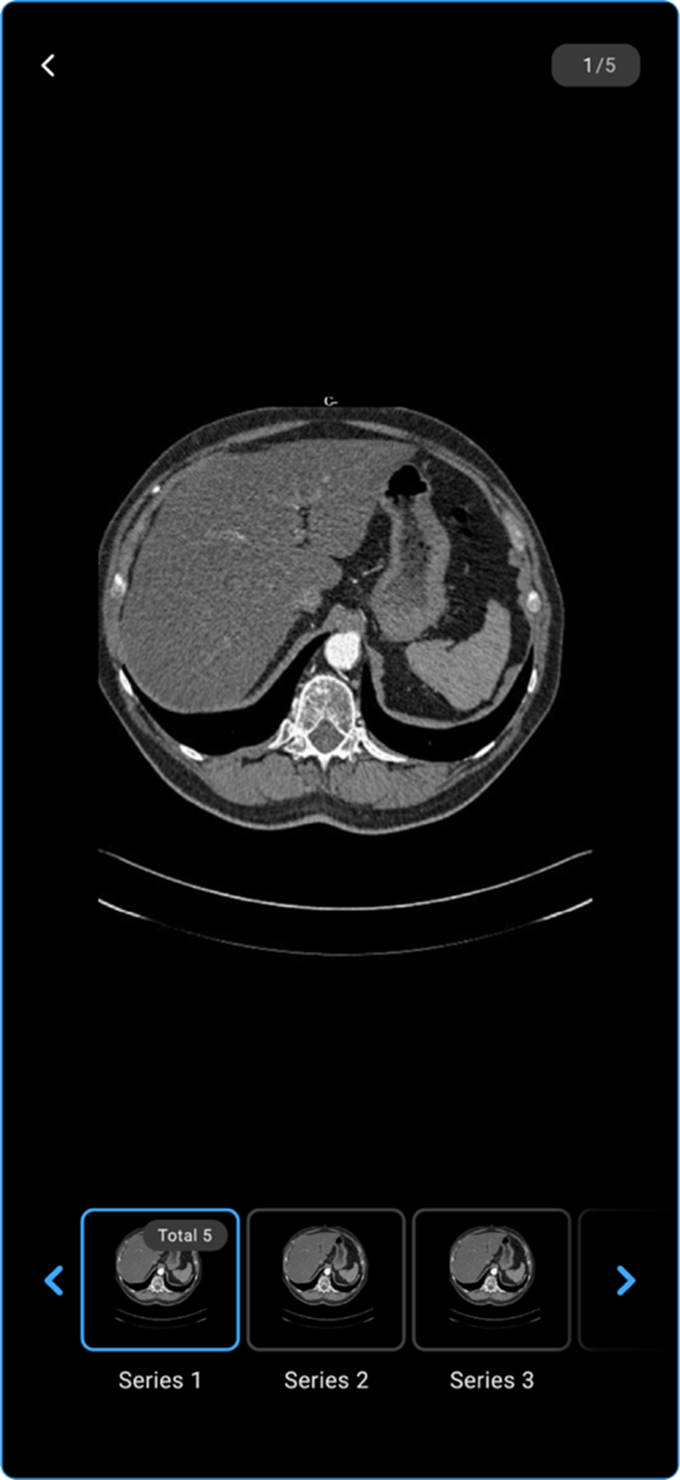

Once you click View Images from the bottom of a completed appointment card (for studies with DICOM images), the Image Viewer opens.

- The available images display in the viewer.

-

View Images — Opens attached study images in the Blume Image Viewer.

a. Swipe up to scroll through series, right to move between frames.

b. Pinch to zoom in or zoom out.

c. Tap the back arrow (top-left) to exit the viewer.

Viewing Images in Completed Appointments

- Go to Completed Appointments and select the desired study.

- Tap View Results to open the Study Information Page.

- Locate and tap View Images to access the available images.

- Scroll sideways to navigate through other images in the series.